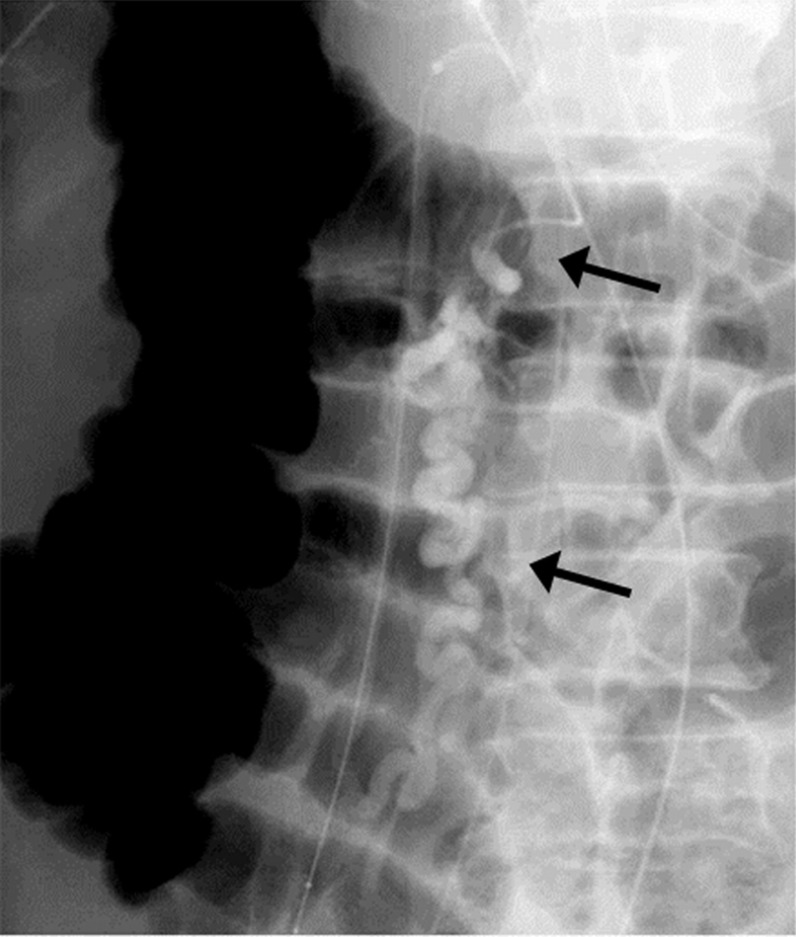

十二指肠静脉曲张是异位门静脉系统分流,不容易导致胃肠道出血。球囊闭塞逆行经静脉闭塞术是治疗胃静脉曲张的常用方法。我们报告一位60岁男性患者,由于起源于胰十二指肠下静脉的十二指肠静脉曲张破裂而导致黑黑;引流到性腺静脉。他的十二指肠静脉曲张破裂成功治疗双球囊闭塞栓塞治疗。

Duodenal varices are ectopic portosystemic shunts that do not tend to result in gastrointestinal bleeding. Balloon-occluded retrograde transvenous obliteration is an established treatment for gastric varices. We report a 60-year-old man with melena due to ruptured duodenal varices originating at an inferior pancreaticoduodenal vein; drainage was into a gonadal vein. His ruptured duodenal varices were successfully treated by dual balloon-occluded embolotherapy.